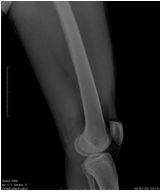

X-ray of the left thigh showed well-defined soft tissue lesion noted on the posterior aspect of lower thigh (Figure 1). There was no calcification, fracture, dislocation and osseous lesion.

Figure 1: X ray of posterior aspect of the lower thigh with well defined lesion